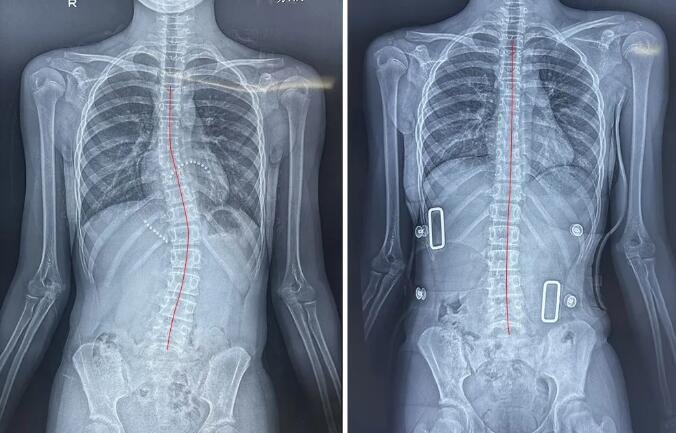

青春期女生调整前(左图)、8节调整课后(右图)